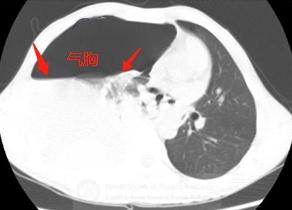

打喷嚏后出现右边胸口疼,呼吸困难,不能深吸气,赶紧上担架车做了急诊CT:

胸部CT显示右侧液气胸,胸腔积液和气体压迫肺组织,导致呼吸困难和不能深吸气,并且挤压心脏向左侧移位。